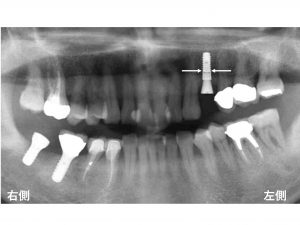

本日最後の症例です。

下顎右側の奥歯が2歯欠損しています。

患者様は、義歯(入れ歯)ではなく、

インプラント治療をご希望されました。

以下は、

先日行ったインプラント手術直後です。

かなり長いインプラントで

かなり太いインプラントが埋入できました。

本日の症例のように

使用するインプラントには、

長さや太さが違うのです。